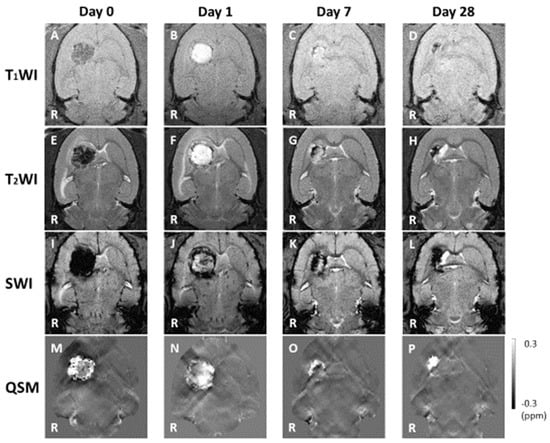

3.1. MRI Observation

3.2. Hemorrhage Signal